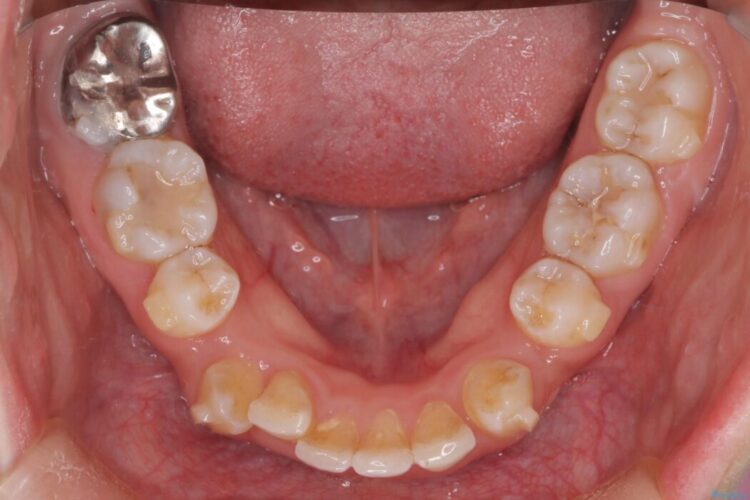

前歯から奥歯にかけて重度のがたつきを主訴にご来院された患者様です。

スペースが大きく不足し、口元を引っ込める必要があったため、上下左右4本抜歯による矯正治療を計画。目立たないインビザライン装置で、審美的なゴールを目指します。